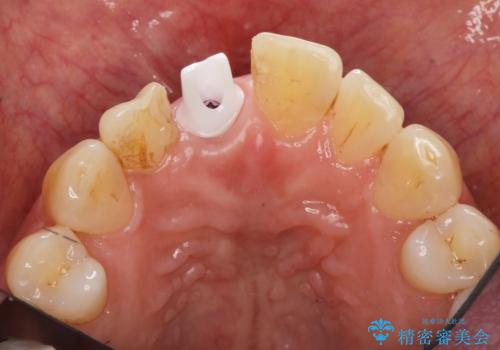

- 前歯を外傷により失い、審美性の改善を求めて来院されました。

横の歯を削る必要のあるブリッジ治療、着脱の必要な入れ歯に強い抵抗があったためインプラント治療を計画します。

審美的・機能的に良好な位置に埋入するには、骨量が十分ではなかったため骨の造成を併用したインプラント埋入外科手術を行います。

前歯のインプラントを審美的に仕上げるには、インプラント周囲に十分な骨の量と厚みのある歯肉、そして埋入位置の精密な位置付けが重要です。